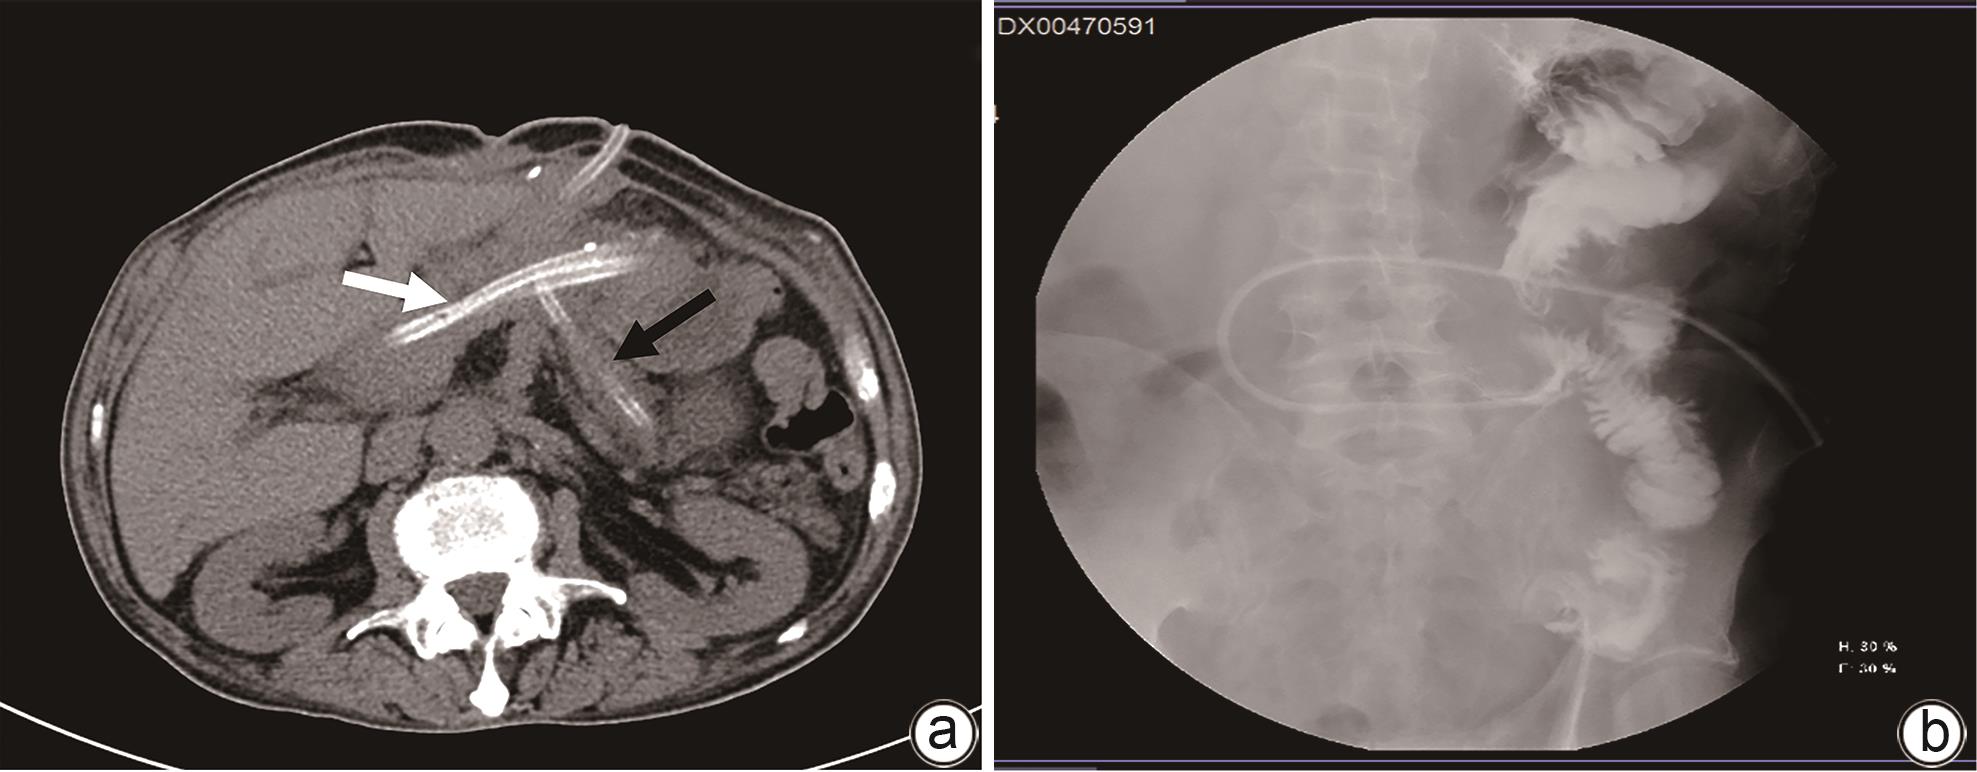

Clinical effect of Foley catheter through sinus tract in treatment of complex pancreatic fistula with massive venous hemorrhage after pancreaticoduodenectomy: A case report

2024, 40(11): 2283-2287. DOI: 10.12449/JCH241123

Abstract:

At present, vascular intervention and surgery are the main methods for the treatment of pancreatic fistula with bleeding after pancreaticoduodenectomy, but these treatment methods have certain drawbacks, such as the complications of pancreatic fistula, bleeding, and abdominal infection after surgical treatment, and interventional treatment sometimes fails to identify the bleeding site. This article reports a case of complex pancreatic fistula with massive venous hemorrhage after pancreaticoduodenectomy treated with Foley catheter balloon compression through the drainage tube sinus. Bleeding was arrested and gastrointestinal fistula was cured after catheter balloon compression and effective drainage, with no complications such as pancreatic pseudocyst, intestinal ischemia, and portal hypertension.